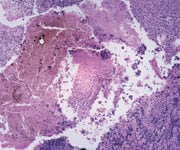

Of the three main types of skin cancer, melanoma is by far the most dangerous. One American dies of melanoma every hour, yet it is virtually 100% curable if detected in time.1 Unfortunately, dermatologists may be missing up to 30% of curable melanomas.1 So you would think that when the FDA is presented with a completely safe, non-invasive device that can help diagnose early melanoma almost instantly, it would receive swift approval. You would be wrong. In this article, you will learn of the agency's ongoing and unconscionable two-year delay in approving MelaFind®, a technologically advanced optical device that boasts a 98% melanoma detection rate. You will also discover how even as the FDA cited baseless concerns over MelaFind®'s "safety", they fast-tracked approval for a costly, mediocre melanoma drug costing $30,000 per dose with potentially lethal side effects. You will also find out how FDA bureaucracy and bias are sending lifesaving medical innovations like MelaFind® overseas—and out of reach for most Americans. Melanoma Detection: Methods, Flaws, and AdvancesUnlike other cancers that start inside the body, melanoma begins on the skin's surface and is typically curable if caught early. But early detection is often dependent on a doctor's ability to make educated decisions on which moles they feel are necessary to biopsy. Dermatologists consider whether or not to biopsy the hardest decision they have to make on an hourly basis. The reason? The average middle-aged Caucasian has 50 to 60 variously colored moles, or lesions, all over the surface of his or her body. While there may be some that squarely fit the profile of a melanoma, frequently patients present with five, ten, or more suspicious moles. To biopsy every suspicious lesion is cost-prohibitive and leaves the patient with multiple incisions and scars for life. Yet the only way to know for sure if a suspicious skin lesion is or is not an early-stage melanoma is to do a biopsy. Dermatologists are thus confronted with critical decisions as to which lesions to biopsy. In that decision, according to Dr. Joseph V. Gulfo, CEO of the company that developed MelaFind®, dermatologists today are missing at least 30% of curable melanomas. They also have to biopsy 50 benign lesions for every melanoma they do find. "Think about that. The value of a false positive is a minimal concern compared to missing a melanoma. Yet doctors are still missing cancerous lesions. They don't want to miss, but they are." Contrast this with MelaFind®, a multi-spectral camera combined with sophisticated algorithms and software to image each potentially cancerous lesion. The image is then compared against a database of more than 10,000 biopsied lesions and 600 confirmed melanomas to provide the dermatologist with an immediate reading.